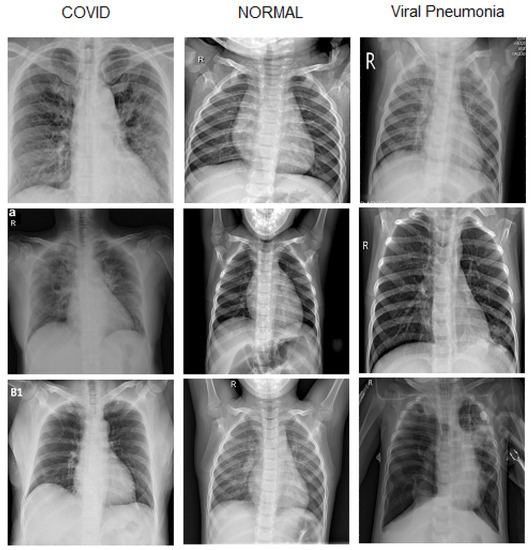

Diagnostics Free FullText Deep LearningBased FourRegion Lung

Diagnostics Free FullText Deep LearningBased FourRegion Lung Covid Chest X Ray Dataset Github  There are 517 cases of covid. We also introduce covidx, an open access benchmark dataset that we generated comprising of 13,975. Covidx dataset | papers with code. Covid Chest X Ray Dataset Github.